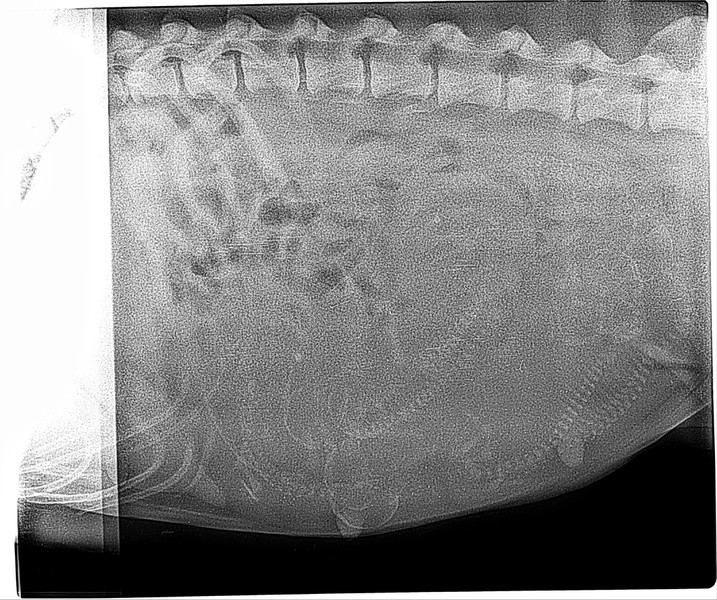

Wir waren zum Wiegen und Röntgen.

Ausgangsgewicht waren perfekte 33,5 kg. Die Waage zeigte nun 41,9kg.

Und dann ging es zum Röntgen.

Und was soll ich sagen, wir sahen genau 6 Babys, 6 Wirbelsäulen.

Und ob ihr mir das glaubt oder nicht, ich habe mir 6 gewünscht und 8 wären auch noch in Ordnung. Egal wieviel, alle werden geliebt aber ich hatte diesen Wunsch.

Noch schnell ein Update, Claudi sieht auf dem Röntgenbild 8 Babys. :-)